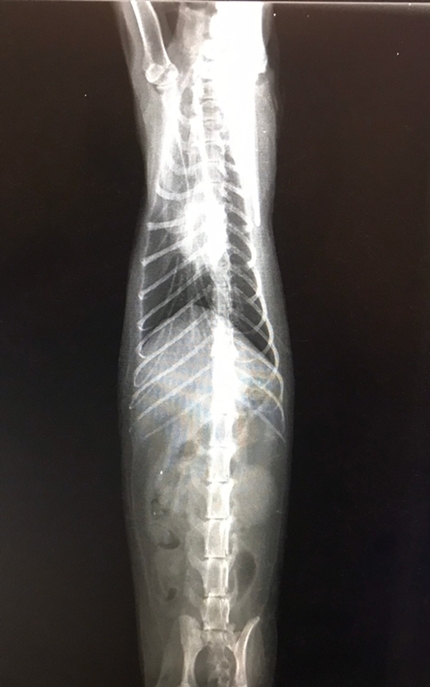

主題: 抽蓄腦震盪疑似車禍貓 申請者姓名: 劉素鳳 花色: 申請日期: 2020-05-29 08:47:36 申請者部落格: 申請者臉書網址: https://www.facebook.com/sufeng.liu 所在縣市/合作醫院: 高雄市/弘恩動物醫院 治療費用: 9800元 需求人數: 39人 已結案 (2024-05-31 18:16:22) 報名人員: 黃茂強 x2(已付款)、御用鏟屎官(已付款)、saxso x2(已付款)、山岳雲海 x2(已付款)、JUN(已付款)、蔡佳玲(已付款)、欣(已付款)、Yi-Yun Wu(已付款)、Evi x15(已付款)、Evi x13、Joyce(已付款)、Jing(已付款)、weiwei(已付款)、martim(已付款)、魚 x2(已付款)、Sarah Xie(已付款)、魚 x2、CBR600RR(已付款)、張維安(已付款)、Linda x3(已付款)、周麗守 x2(已付款)、 候補人員: 動物病情說明: 看到路邊抽蓄疑似被車撞的貓咪送往醫院治療

到院後有發燒感染不吃的狀況

醫生幫貓咪做了x光還有血檢,感謝醫院細心照顧餵食與藥物治療,貓咪的狀況總算穩定下來動物近況說明: 目前貓咪暫時安置著,讓他補補身子,好好休養,大難不死必有後福,感謝大家的幫忙。